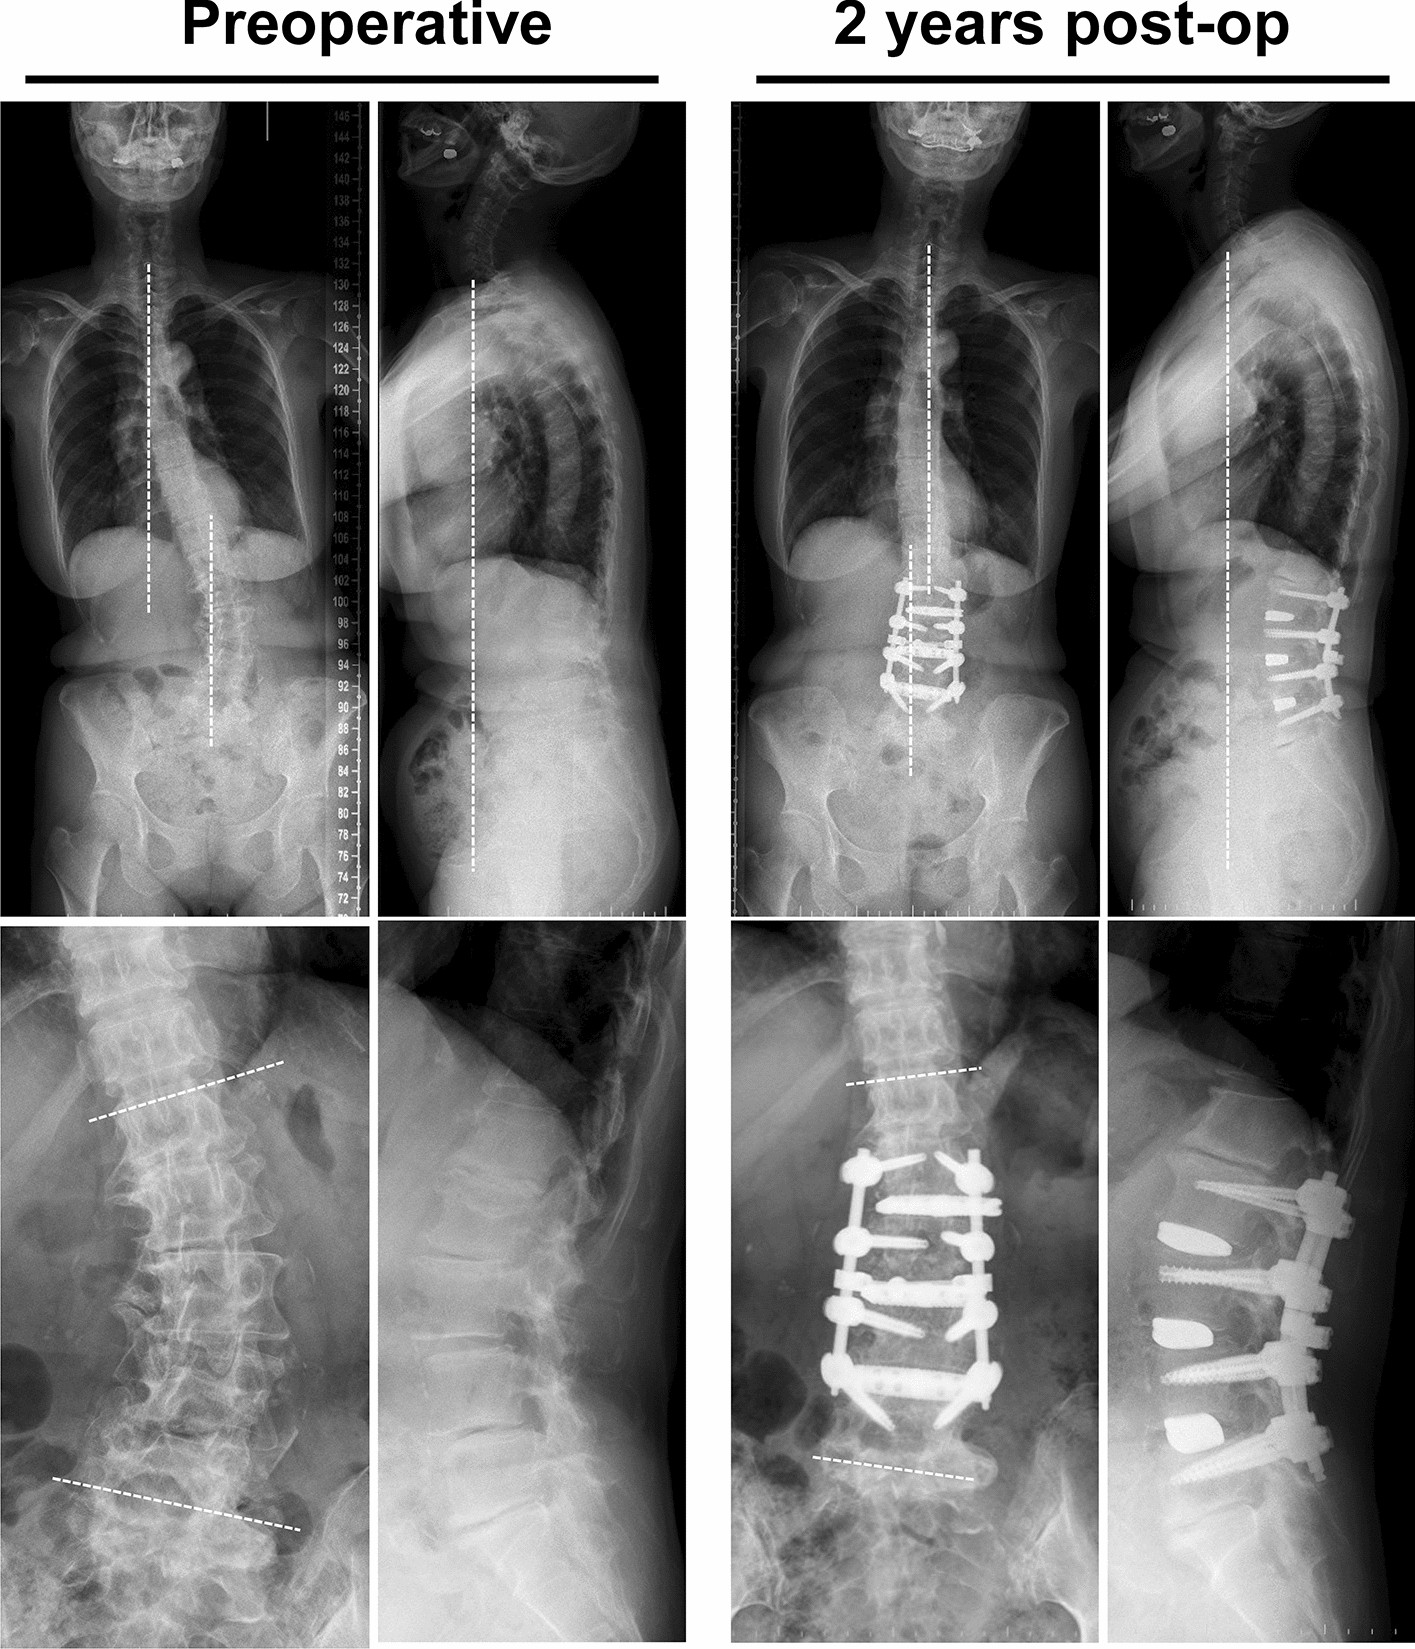

Figure 3

A 68-year-old female with gait disturbance mainly due to frontal trunk tilt. Preoperative radiological parameters showed poor global alignment with Cobb angle 30.6°, coronal decompensation 59.9 mm, C7 SVA 116 mm, and PI-LL 18.4°. These parameters improved to 1.4°, 6.1 mm, 62.5 mm, and 15.9°, respectively, at 2 years after surgery.